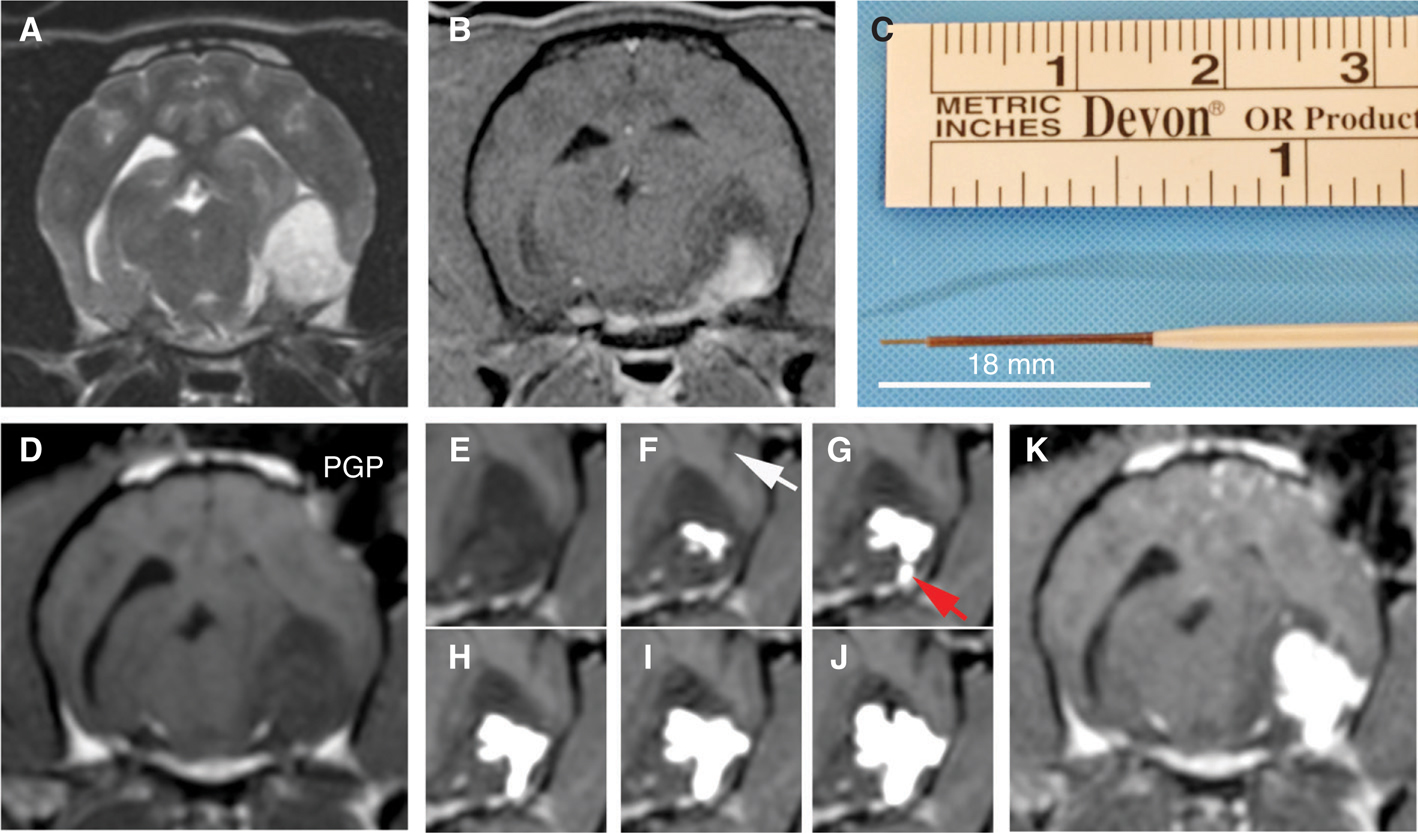

Canine subjects enrolled in the trial have mild-to-moderate clinical signs of brain dysfunction and histopathologically confirmed gliomas demonstrating immunoreactivity to IL-13RA2 and/or EphA2. The trial is designed using a 3+3 dose-escalation scheme, with cohorts administered 0.05, 0.1, 0.2, or 0.4 μg of each cytotoxin/ml of infusate. To optimize the CED procedure, an inverse therapeutic planning method, using a spherical shape–fitting algorithm generated from patient-specific, segmented MRI/CT images, is used to simulate ideal cannula placement and target coverage prior to treatment (69, 70). CED is performed in the anesthetized dog using reflux-preventing cannulae to co-administer the cytotoxins with a gadolinium tracer (Figure 2) to allow for intraoperative MRI visualization of infusate distribution. Tolerability is defined as the absence of dose-limiting toxicities (DLT) within 28 days of infusion. DLT are considered the development of Grades 3, 4, or 5 adverse events, as defined by the Cancer Therapy Evaluation Program CTCAE standards (71). Serial clinical, laboratory, and brain MRI examinations are performed for 6 months following CED treatment, and the CED infusions can be repeated in the event of tumor progression or suboptimal target coverage is achieved during the initial infusion. Efficacy is determined by characterizing objective tumor responses using RANO and volumetric criteria modified for use in canine patients (72).

Fig 2

Figure 2 Intratumoral convection-enhanced delivery (CED) of molecularly targeted therapeutics into a canine astrocytoma. Pre-treatment transverse T2-weighted (A) and post-contrast T1-weighted (B) images demonstrating the tumor in the temporal-piriform lobes of the brain. (C) Fused silica and ceramic reflux-preventing cannula (RPC) with multistep tip design used for CED. (D) Intraoperative, transverse T1-weighted images obtained immediate prior to infusion, showing probe guide pedestal (PGP) implanted in the skull, through which RPC (F, white arrow) will be stereotactically placed into the tumor. (E–J) Time-lapsed 3DT1-weighted images taken over approximately 2 h of MR-monitored infusion showing progressively increasing volume of distribution of the infusate co-delivered with gadolinium (white) within the tumor. An additional RPC has been inserted (G, red arrow) to facilitate tumor coverage. (K) Immediate post-infusion T1-weighted image demonstrating tumor coverage and infusate containment achieved at completion of CED.

Using this approach, we have achieved robust and clinically relevant volumes of infusate distribution in unresected canine MGs (Figure 2). In addition, inclusion of real-time MR-monitoring-facilitated intraoperative cannulae revisions that allowed continued target coverage after observation of ventricular leakage or infusate reflux in some procedures. Clinical and partial tumor volumetric responses (≥50% volumetric tumor reductions) have been observed in 55% (5/9) of the dogs treated to date. Necropsy examinations performed in four dogs with progressive disease have revealed tumor necrosis in infused regions. In the first three dosing cohorts, significant DLT have not been observed. Results from this trial indicate that improvements in CED cannula design, therapeutic planning, and MRI monitoring allow for safe and effective intratumoral delivery of IL-13RA2- and EphA2-targeted cytotoxins. This ongoing study also provides preliminary evidence of the efficacy of these cytotoxins when used as a monotherapy in a spontaneous animal glioma model.